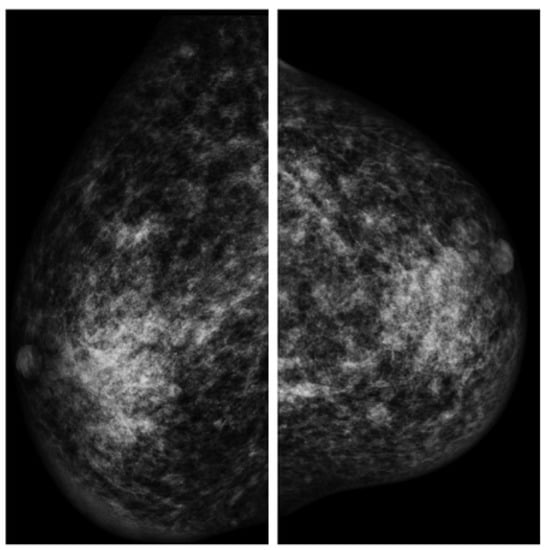

The patient underwent mammography, mammary ultrasound, agobiopsy (TRU-CUT), and serum exams in order to examine his clinical condition from 2015 to 2016 (Figure 2).

Several mammary simple cysts, with diameters ranging between 5 and 30 mm, suggestive of fibroadenomas, and a dense fibroglandular breast parenchyma were reported by the radiologist, who described these radiological findings as uneven in a “normal” gynecomastia.

Figure 2. Mammography findings (left and right breast).